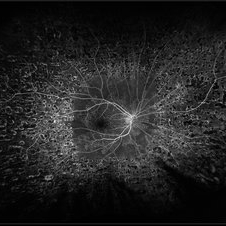

Composite fluorescein angiogram of the left eye of a male with a Central Retinal Vein Occlusion with severe ischemia.

Photographer: Olivia Rainey

Imaging device: Heidelberg Spectralis

Condition/keywords: central retinal vein occlusion (CRVO), composite, fluorescein leakage, ischemic CRVO